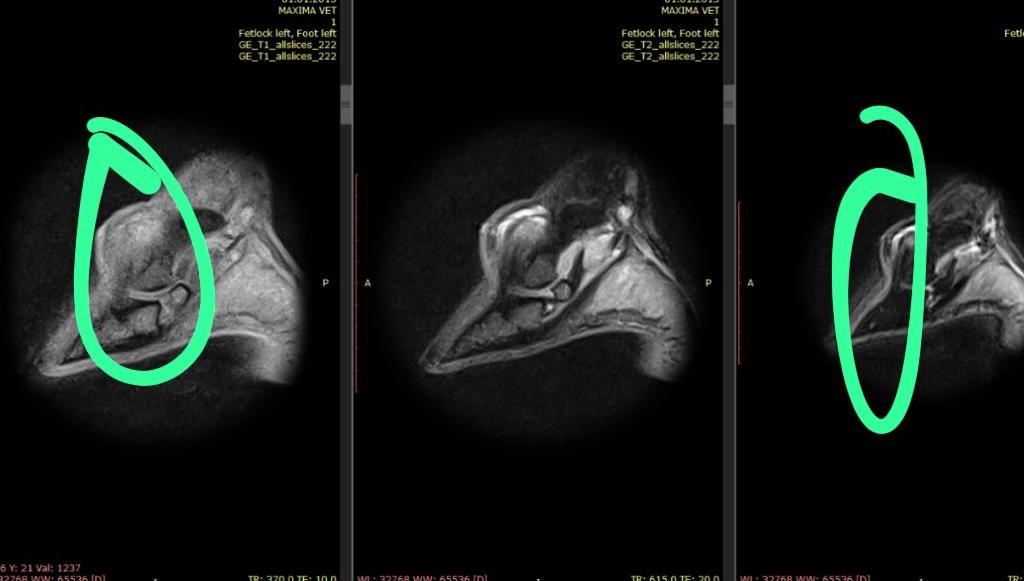

Данный пациент одним из первых попал в очередь на МРТ-обследование, имея определенную зону для обследования, постановку точного диагноза и планирования дальнейших прогнозов для спортивной карьеры.

Левая грудная конечность: переполнение и синовит копытного сустава, навикулит,

киста копытной кости.

Находки, которые определили при МРТ-исследовании, дают точный и полный

диагноз для обследуемой зоны. И самое важное – определяют возможность для

данной лошади спрогнозировать шансы возвращения в спорт, а также получить

более полную консультацию от ветеринара по консервативному и хирургическому

лечению.